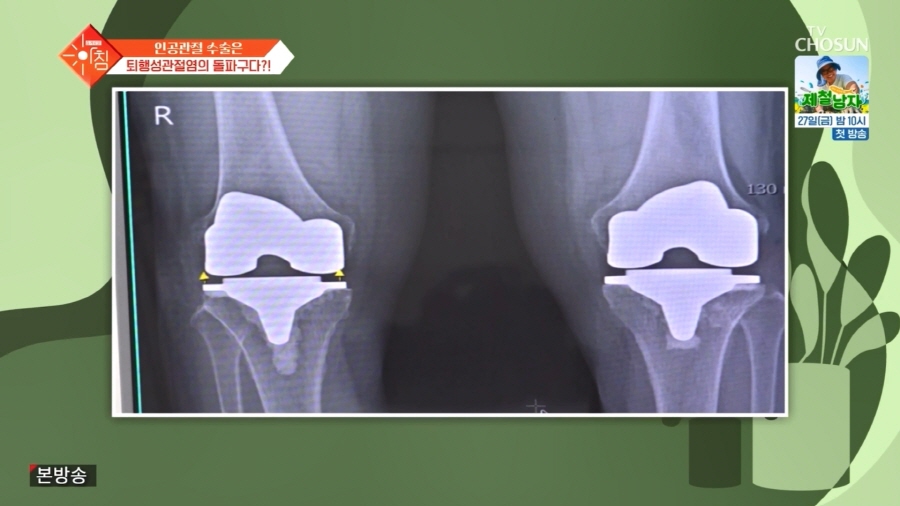

TV조선 <슬기로운 아침> 무릎 퇴행성 관절염 편에

이번 방송에서는 관절염 조기 치료의 필요성과 치료 방법에 대해 자세히 설명드리고,

실제 무릎 관절염으로 보존적 치료를 받는 환자분과

4기 퇴행성 관절염으로 인공관절 수술을 받은 환자분의 사례를 바탕으로

무릎 건강을 조기에 관리해야 하는 이유에 대해 다뤘는데요.